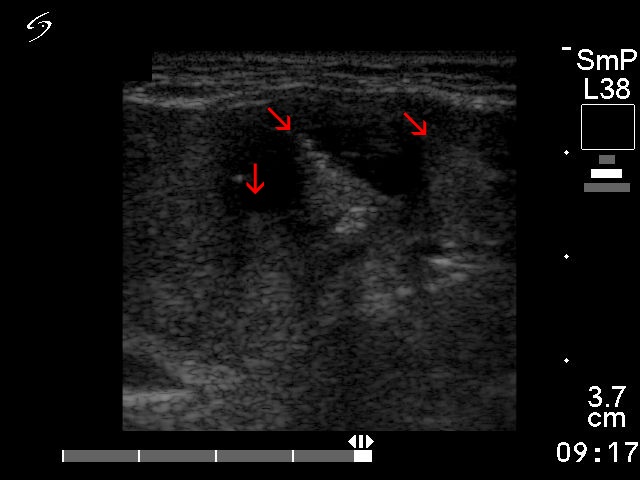

At first sight, both nodules seem to belong to projecting eccentric type. However, solid portions can be observed along the inner wall of the benign lesion (yellow arrows). Therefore, this belongs to the central subtype. The malignant nodule has more projections marked with red arrows.